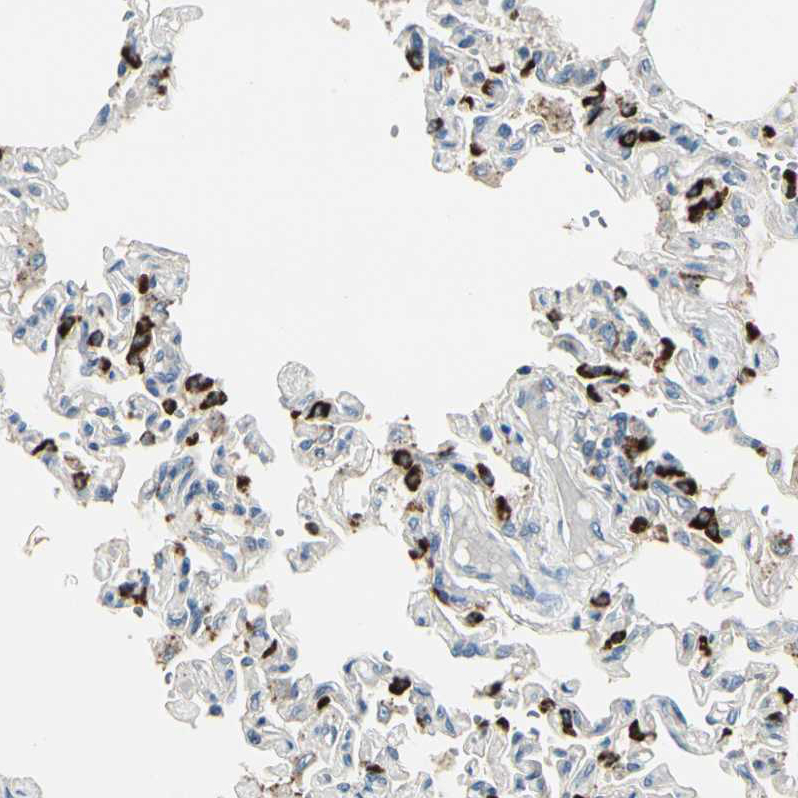

Immunohistochemistry analysis in human lung and cervix, uterine tissues using HPA007884 antibody. Corresponding ABCA3 RNA-seq data are presented for the same tissues.